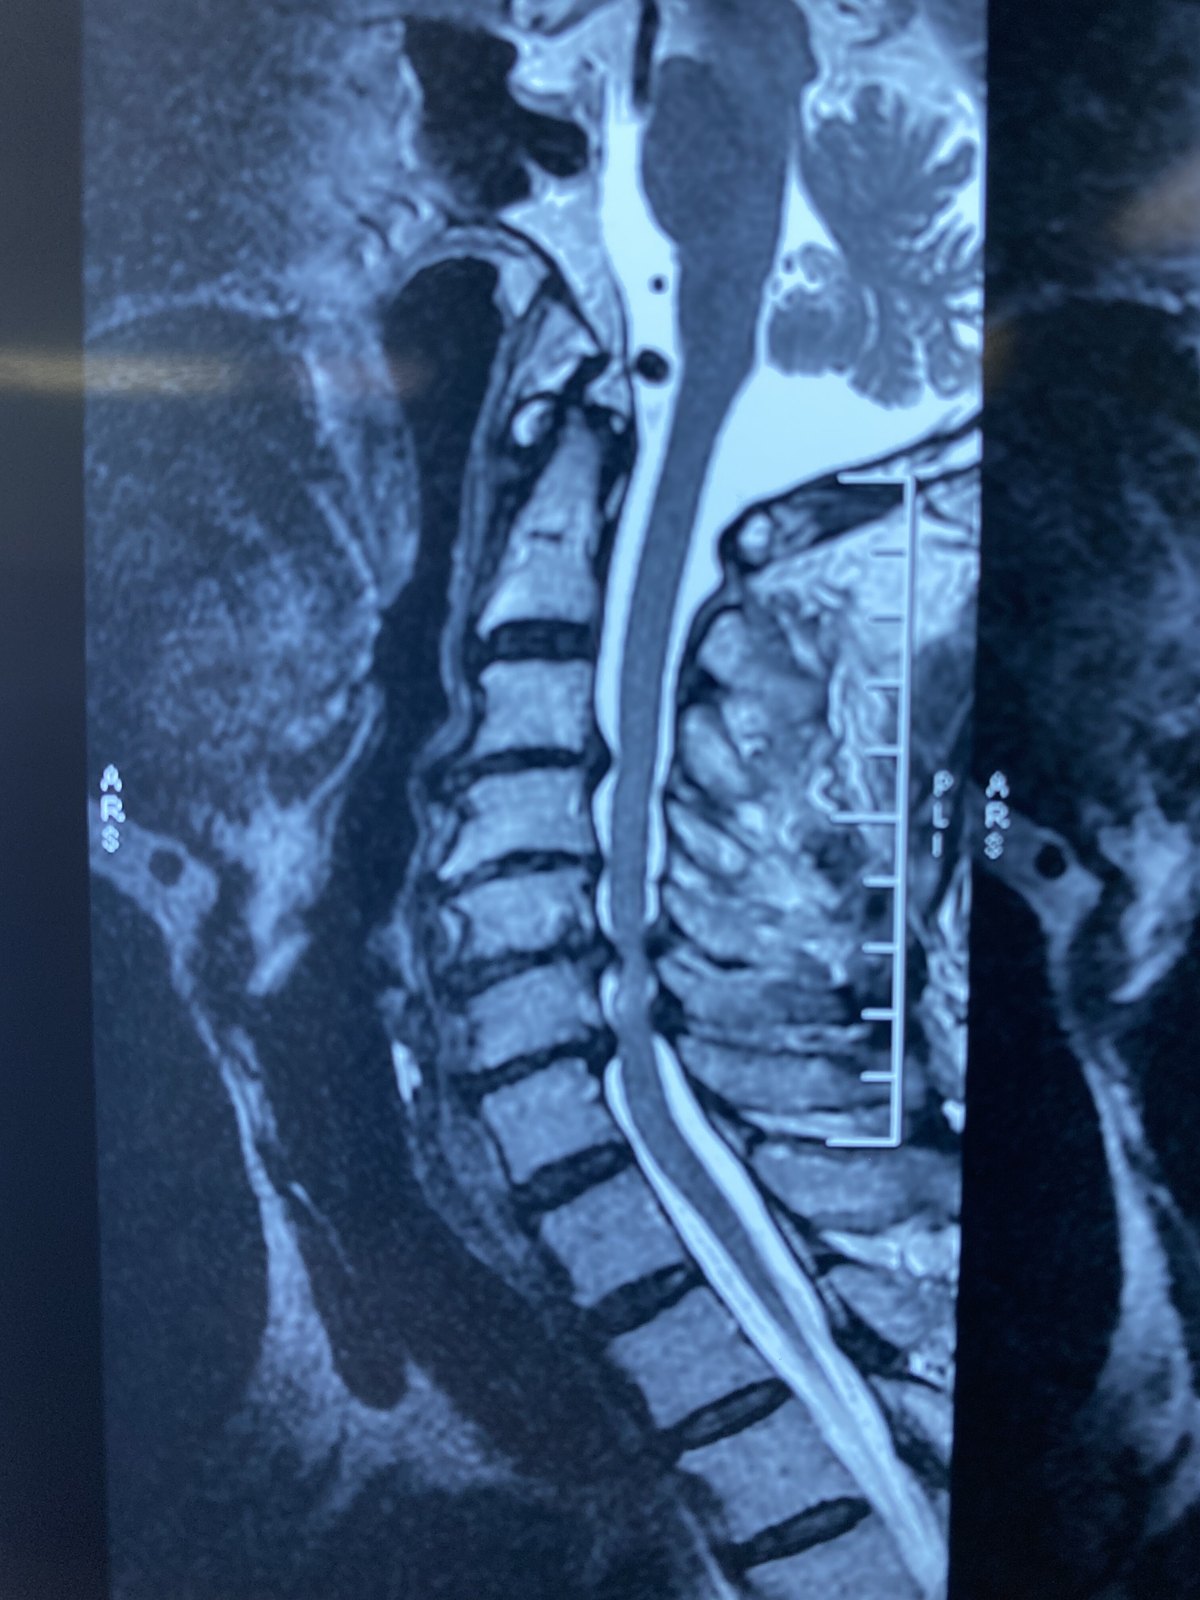

一个标准的颈椎间盘突出的磁共振图像

图片尺寸1080x1178